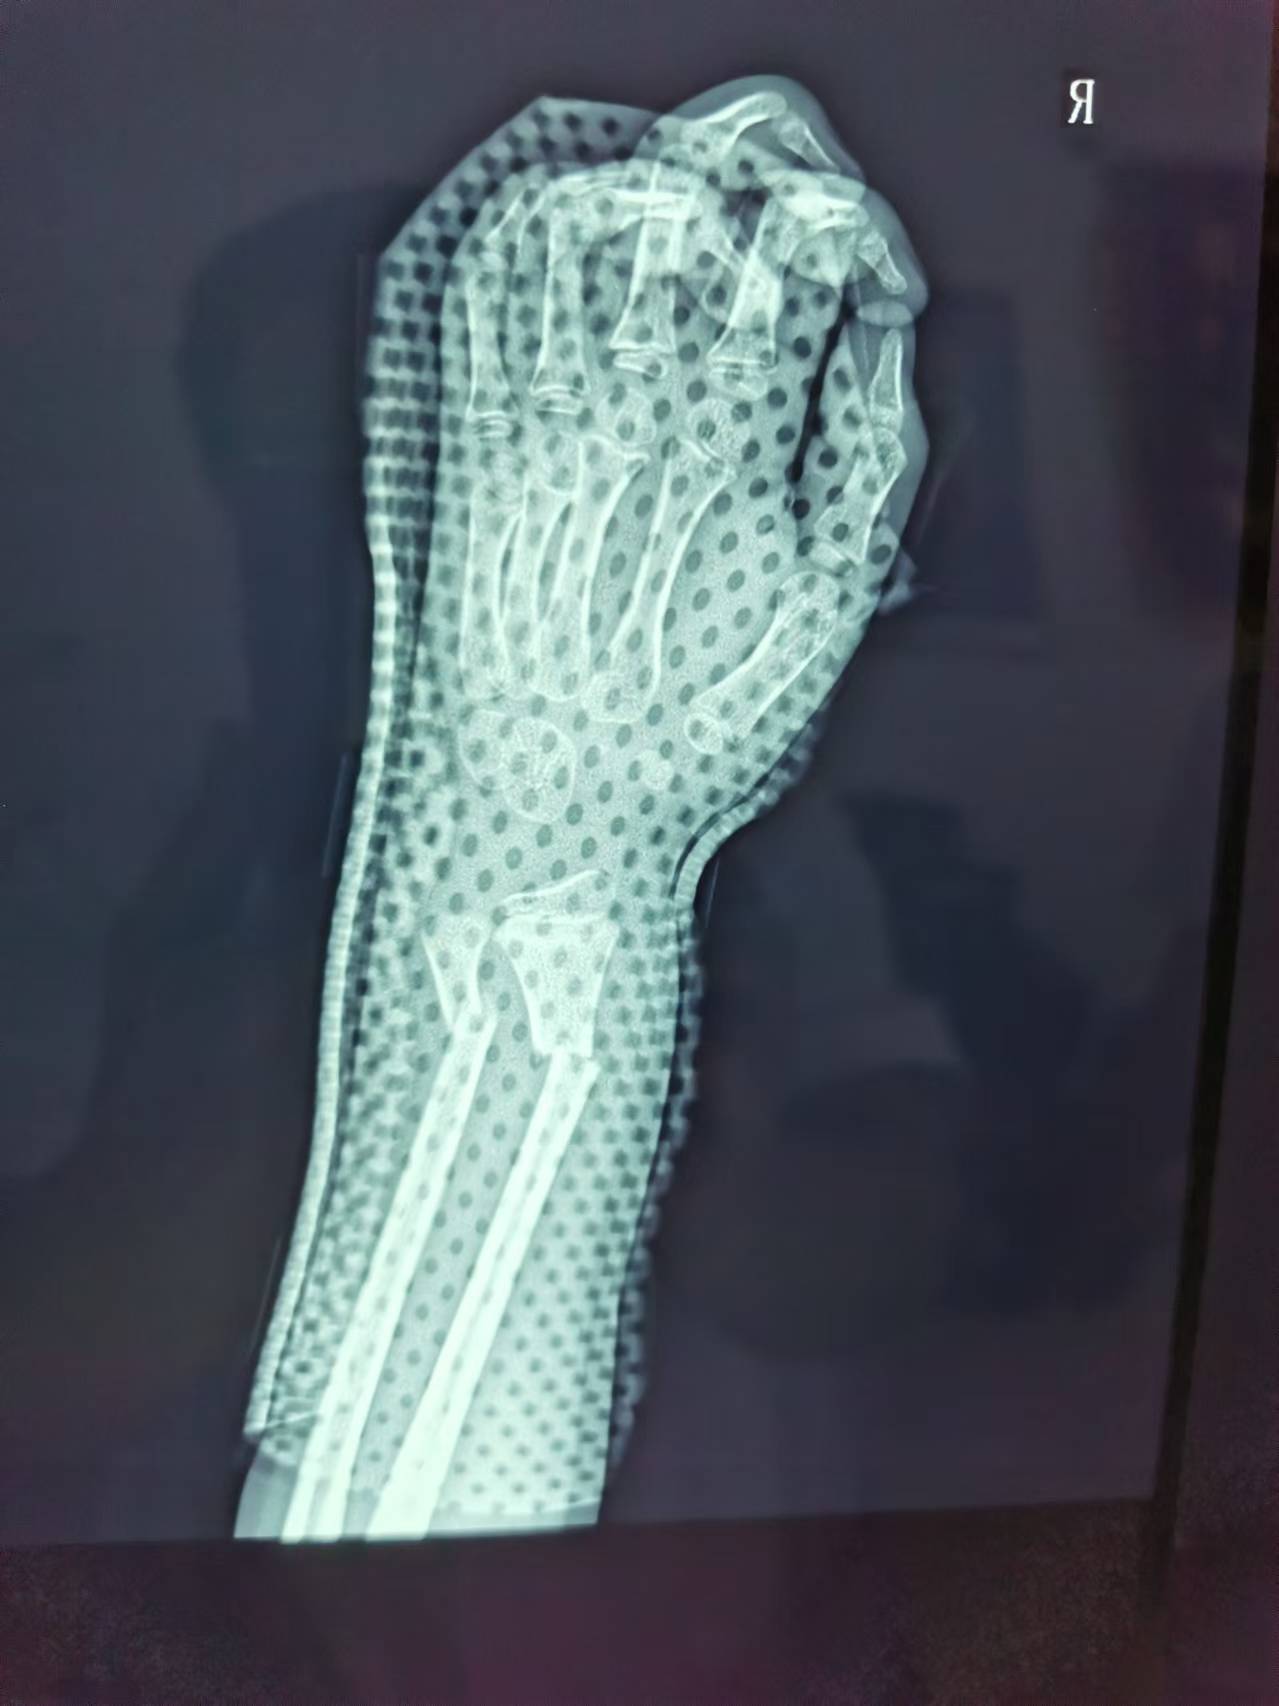

首页 > 张恒云工作室 > 影像资料 一